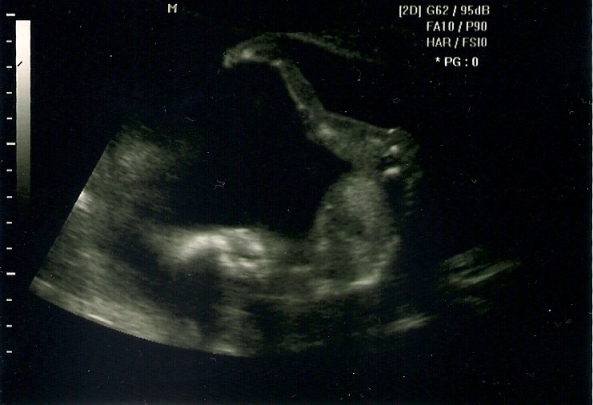

Mercy: Nagyon cuki a kis szégyenlős babód, hogy direkt eltakarta magát. Örülök, hogy minden rendben, + hogy végre érzed a mocorgást éshát azok a tappancsok az UHképen.... halál édes!

(Jah... és mostmár biztos, hogy egyedül van!

)